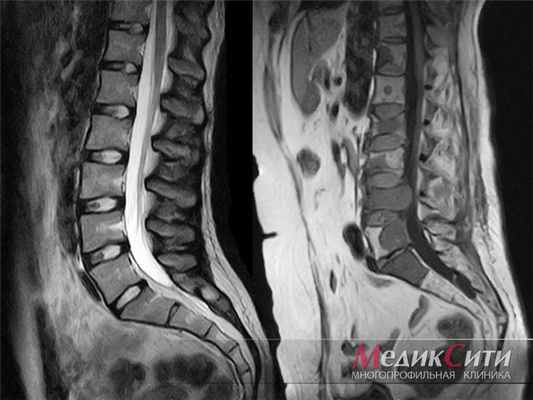

МРТ поясничного отдела позвоночника: 1. норма 2. метастазы

МРТ пояснично-крестцового отдела позвоночника позволяет получить снимки (или как их называют, срезы) тел позвонков, межпозвонковых дисков, конуса спинного мозга и элементов «конского хвоста» и т.д.

- протрузий и грыж межпозвонковых дисков поясничного отдела позвоночника;